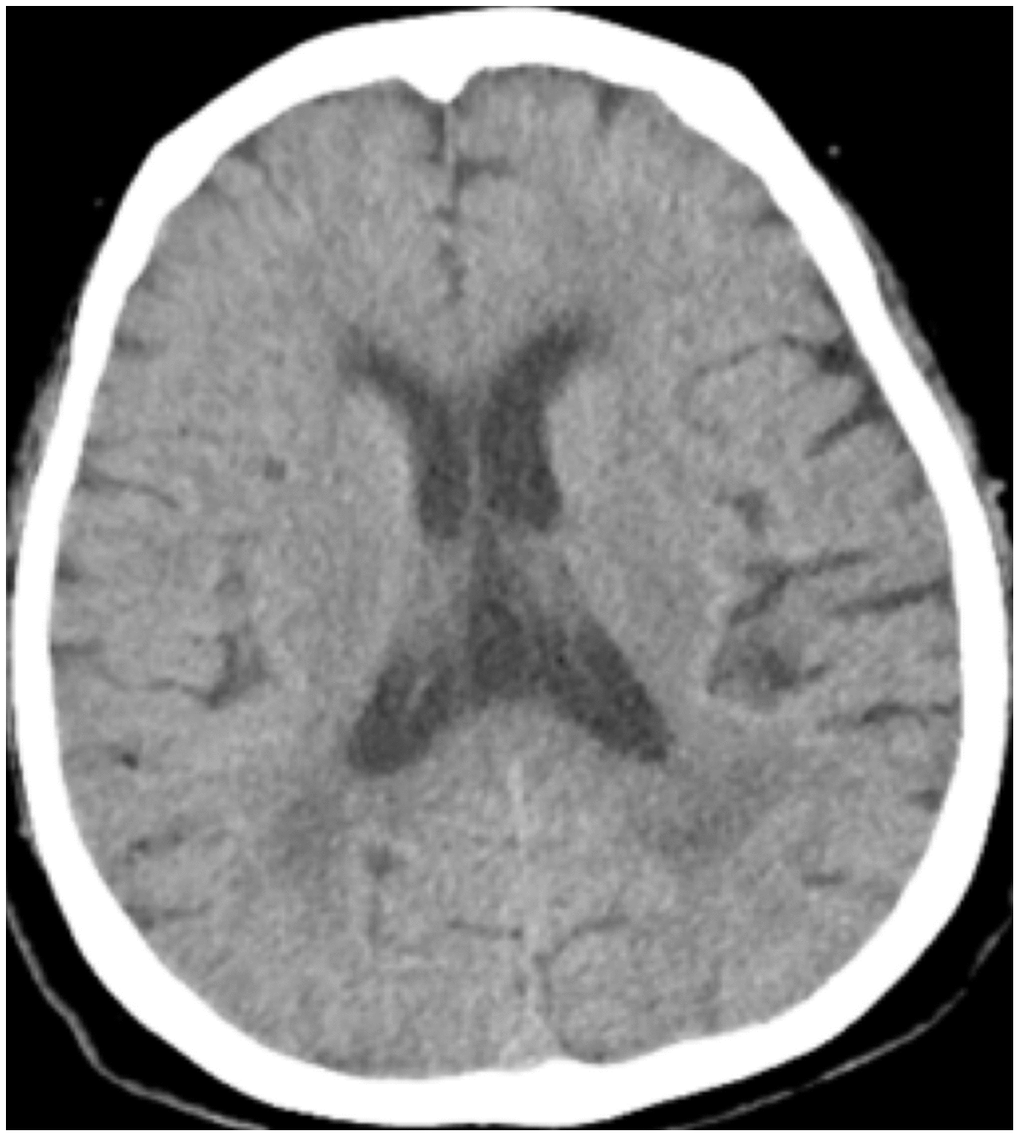

All patients were positive for the coronavirus nucleic acid test from pharyngeal swabs or blood. The blood lymphocyte counts and proportions of all patients were lower than normal (0.8×109/L) at the time of admission, and the white blood cell counts and proportions of six patients were higher than normal value (10×109/L). The blood D-dimer levels in all patients were higher than normal value (243 ng/mL) before neurological symptoms, and the C-reactive protein values in all patients were also higher than normal value (8000 μg/L). The chest CT of all patients showed flaky or frosted glass like- high-density shadow in lungs (Figures 1, 2), pleural effusion was seen in 2 cases (Figure 3), and no obvious abnormalities in 4 cases. The head CT imaging indicated that one patient had brainstem hemorrhage with ventricular cast and hydrocephalus (Figure 4), two patients had a large area of uniform low-density shadow on the frontotemporal lobe on the head CT (Figure 5), four patients had multiple flaky low-density shadow on the parietal lobe (Figure 6), one patient showed flaky low-density shadow in the pons (Figure 7), and three patients could see point-like low density shadow in basal ganglia (Figure 8).

Figure 6. Case 6 multiple flaky low-density shadow on the parietal lobe.

Figure 8. Case 11 point-like low density shadow in basal ganglia.